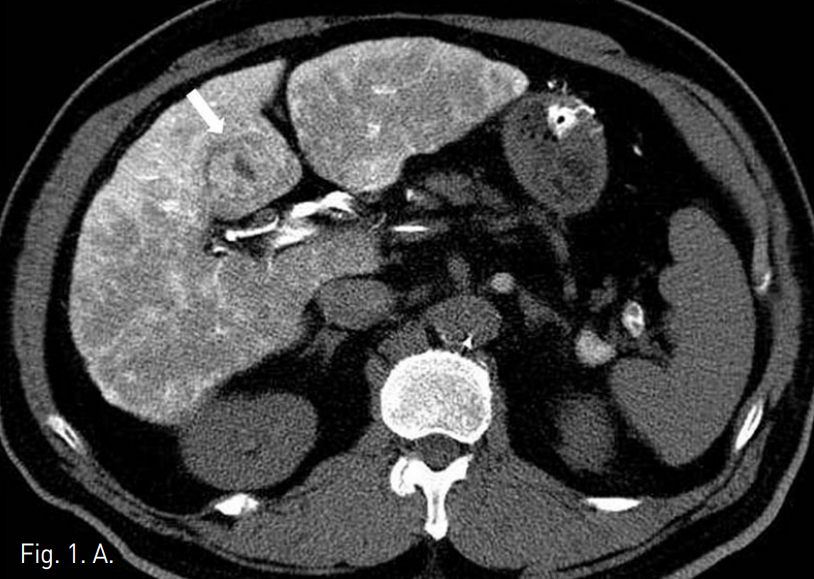

TACE중 실시한 CT during hepatic arteriography (CTHA) (Fig.1A)와 간동맥조영술(Fig.1B)에서 S4의 병변이 저혈관성의 종괴로 보인다. TACE이후 시행한 lipiodol CT 에서 lipiodd의 침착이 충분하지 않았다(Fig.1C).

A. CTHA shows a hypovascular mass (arrow) at hepatic segment IV.

4F Yashiro catheter (Terumo, Japan)를 이용한 간동맥조영술에서 faint tumor staining이 관찰되었고 이어 시행한 CTHA에서도 병변이 저혈관성 종괴로 보였다. 2F Progreat catheter (Terumo, Japan)와 Fathom (Boston scientific, USA) 유도철사로 종양혈관을 superselection 하고 Adriamycin 15mg과 lipiodol 2.3cc mixture를 이용하여 chemoembolization을 시행하였다.